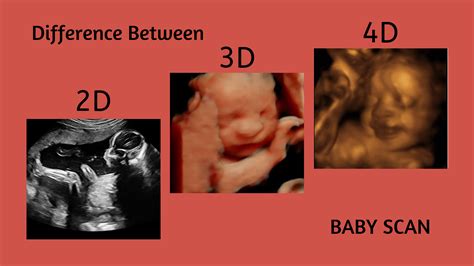

Before we pinpoint the perfect date, it helps to understand the difference between the standard 2D image and the newer, more detailed 3D and 4D versions. They all use sound waves to create images, but the visualization techniques vary significantly.

A 2D ultrasound provides flat, cross-sectional views, which look shadowy and are primarily used for health assessment. A 3D sonogram, however, captures multiple two-dimensional images and uses sophisticated software to reconstruct them into a three-dimensional volume.

This allows you to see surface features—like the curve of your baby's nose, the shape of their lips, and even tiny fingers and toes. Think of 3D as a static photo, providing depth and realism that 2D cannot achieve. It's truly incredible to see!

If 3D is a photograph, 4D is a live video feed. The "fourth dimension" is time. A 4D sonogram captures the same detailed three-dimensional images but continuously streams them, allowing you to watch your baby move, yawn, suck their thumb, or even wave at the camera in real-time.

Many elective ultrasound studios offer 3D/4D packages simultaneously, as the technology required is fundamentally the same. The choice usually comes down to whether you prefer a stunning still image or a live recording of your baby's activities.